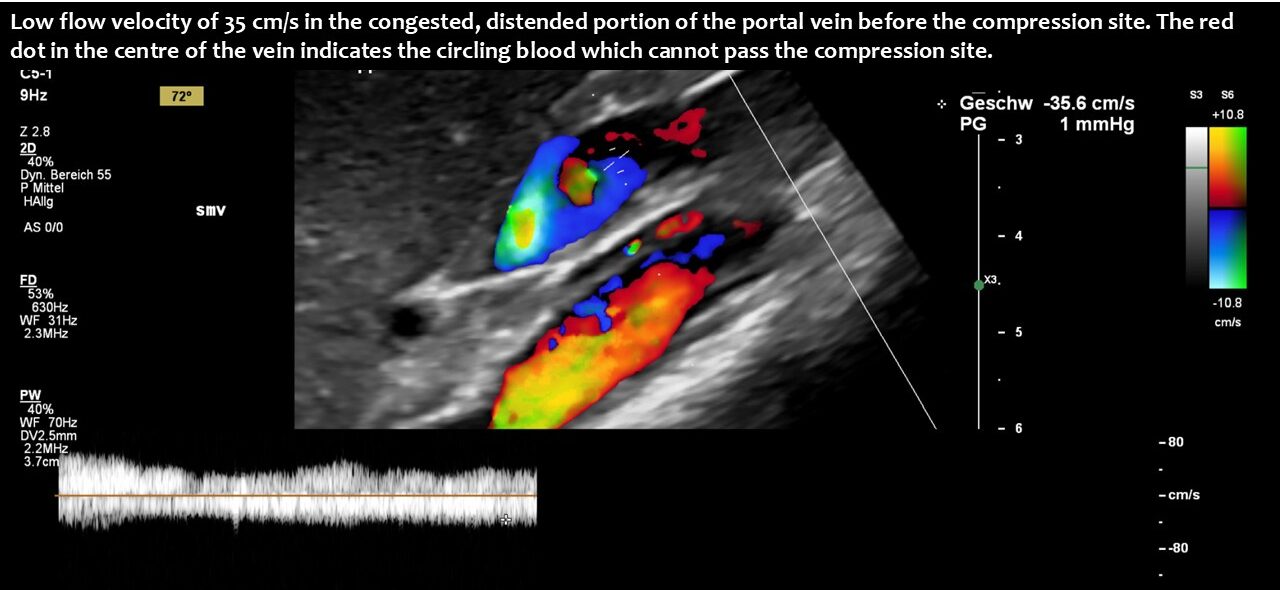

Compression of the superior mesenteric vein and its distension not only compresses the duodenum, but also reduces venous return from the small bowel, which can impair food absorption. Blocked blood flow at the compression site can be demonstrated by a whirling blood stream in front of the compression. Subsequent layers demonstrate antegrade and retrograde flow, as can be seen in the layering of blue and red flow inside the enlarged vein, pointing to changing flow directions and the different flow directions in these layers as highlighted by the spectral analyses at the bottom of the image.